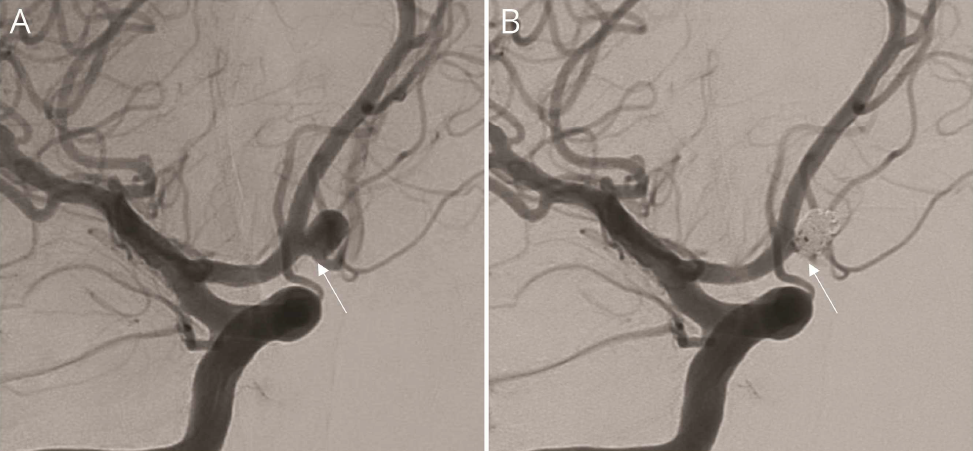

未破裂前交通动脉瘤弹簧圈栓塞术。动脉瘤颈完全闭塞,并且交通段闭塞(图1-A,B)。

病人醒来时伴有顺行性遗忘症,没有其他神经功能缺损。MRI显示穹窿前柱和胼胝体膝部缺血性卒中(图1-C)。重新复习3DSA(3D血管造影重建)重建,证实胼胝体下动脉起源于动脉瘤瘤颈(图1-D)。